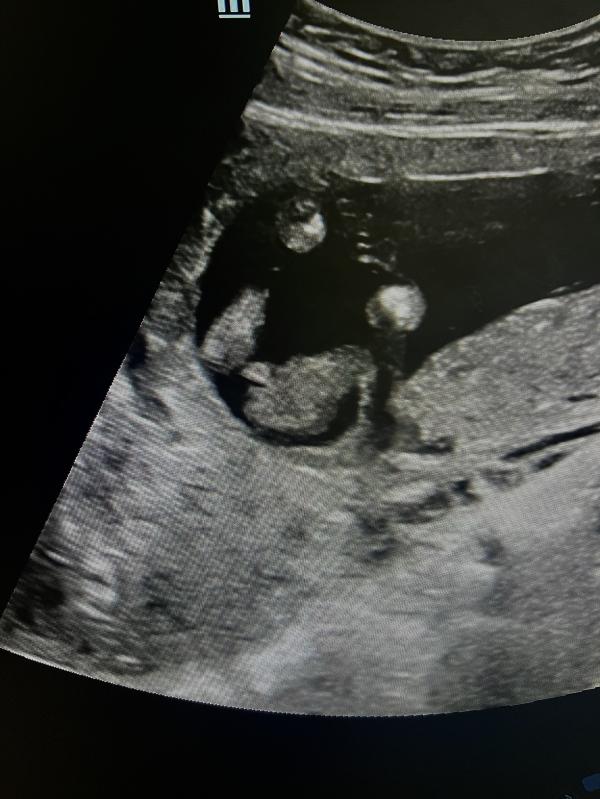

Кто родится: мальчик или девочка? Мнение врача

Девочки,как думаете кто это?

Врач предполагает мальчика

Сегодня на узи и «перчик» показали,но опять же,это не точно😄